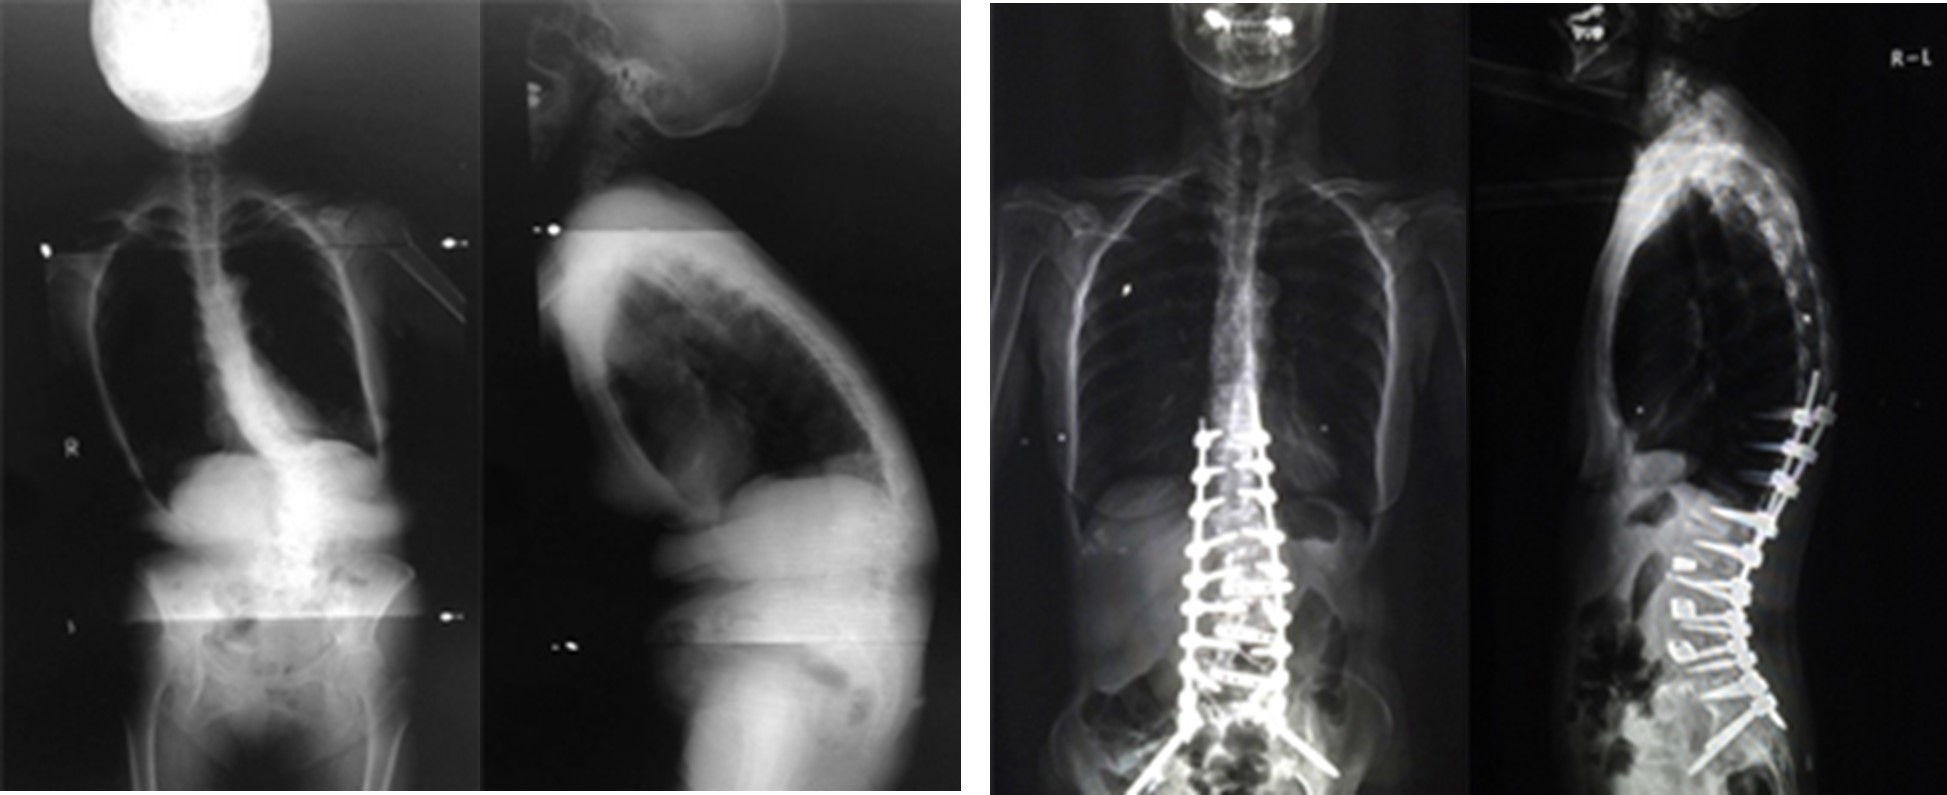

図 (左)術前は、脊椎(せぼね)の彎曲により体幹のバランスを保てず、右側および前方に体が大きく傾いていました。強い腰痛で数分しか立てず、日常生活が著しく制限されていました。

(右)本症例では、人工スペーサーや金属性のスクリューなどを用いた矯正固定術を行い、姿勢バランスとともに臨床症状も著明に改善しました。最近では、側方経路腰椎椎体間固定術(Lateral Lumbar Interbody Fusion: LIF)や、経皮的椎弓根スクリュー(Percutaneous Pedicle Screw: PPS)をはじめとした体への負担を軽減する手法も取り入れられています。